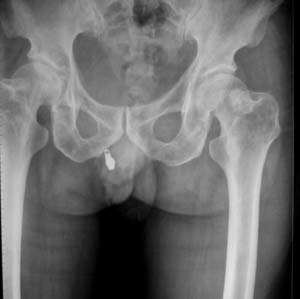

男,61岁,左侧髋关节疼痛,负重后更明显

现上传ct片

左侧股骨头增密,其内见有囊变密度减低区,关节面骨质硬化,关节间隙及髋臼无异示。考虑股骨头缺血坏死可能。建议mri检查。

我觉得股骨头未见到明显的问题,左侧股骨颈有卵圆形高密度影,考虑骨岛或骨梗死。

1\\左侧股骨颈有卵圆形高密度影,考虑骨岛或骨梗死。2\\由于临床症状疼痛,应该mri检查排除早期股骨头缺血坏死

左侧股骨颈处一卵圆形密度增高影,边界清,临近骨组织未见明显破坏.考虑为骨梗死,骨岛?